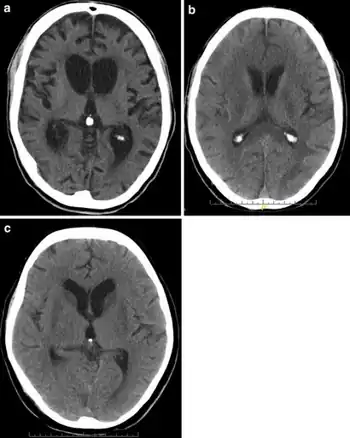

| A CT of the head years after a traumatic brain injury showing an empty space where the damage occurred, marked by the arrow | |

There are several imaging techniques that can aid in diagnosing and assessing the extent of brain damage, such as computed tomography (CT) scan, magnetic resonance imaging (MRI), diffusion tensor imaging (DTI) magnetic resonance spectroscopy (MRS), positron emission tomography (PET), and single-photon emission tomography (SPECT). CT scans and MRI are the two techniques widely used and are most effective. CT scans can show brain bleeds, fractures of the skull, fluid build up in the brain that will lead to increased cranial pressure. MRI is able to better to detect smaller injuries, detect damage within the brain, diffuse axonal injury, injuries to the brainstem, posterior fossa, and subtemporal and subfrontal regions. However, patients with pacemakers, metallic implants, or other metal within their bodies are unable to have an MRI done. Typically the other imaging techniques are not used in a clinical setting because of the cost, lack of availability.[36]